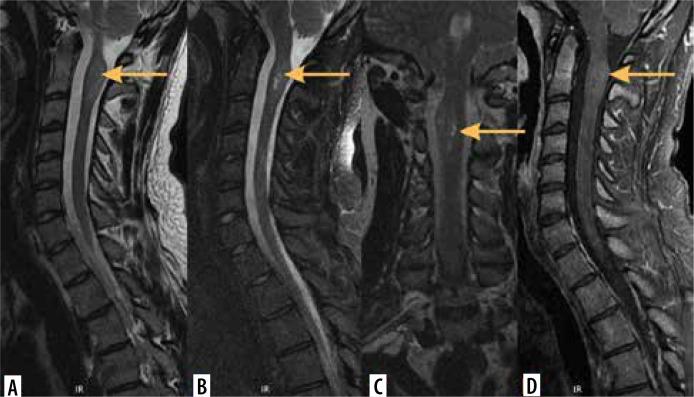

脊髓髓内肿瘤的影像学检查

Imaging of intramedullary tumours of the spinal cord.

Intramedullary tumours (IMTs) are the least common neoplasms of the spinal canal. The majority of them are ependymomas and astrocytomas, the third commonest is haemangioblastoma, while other tumours of the spinal cord are relatively rare. This review presents on update on the imaging of spinal cord tumours. Magnetic resonance imaging (MRI) is the imaging method of choice in diagnosing IMTs, with other modalities playing a supplementary role. The authors discuss the MRI protocol in IMTs including advanced techniques and present the imaging features of particular tumours. The differentiation of IMTs from other spinal cord diseases is also presented.

摘要

髓内肿瘤(IMTs)是椎管内最不常见的肿瘤。其中大多数是室管膜瘤和星形细胞瘤,第三常见的是血管母细胞瘤,而脊髓的其他肿瘤相对少见。本综述介绍了脊髓肿瘤成像的最新情况。磁共振成像(MRI)是诊断IMTs的首选成像方法,其他方式起辅助作用。作者讨论了IMTs的MRI检查方案,包括先进技术,并介绍了特定肿瘤的成像特征。还介绍了IMTs与其他脊髓疾病的鉴别诊断。